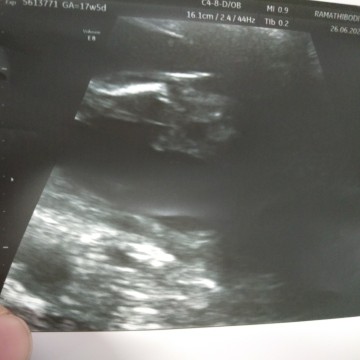

มีแม่ๆคนไหนรู้ไหมคะนี่คือส่วนไหน หมอปริ้นมาสองใบ ใบข้างบนคือศรีษะพอจะดูออก แต่ตรงนี้ คือส่วนไหนคะ 17w กว่าค่ะ ไม่ได้ถามหมอมาค่ะอันตร้าซาวน์แล้ว ออกมาพบหมออีกคน